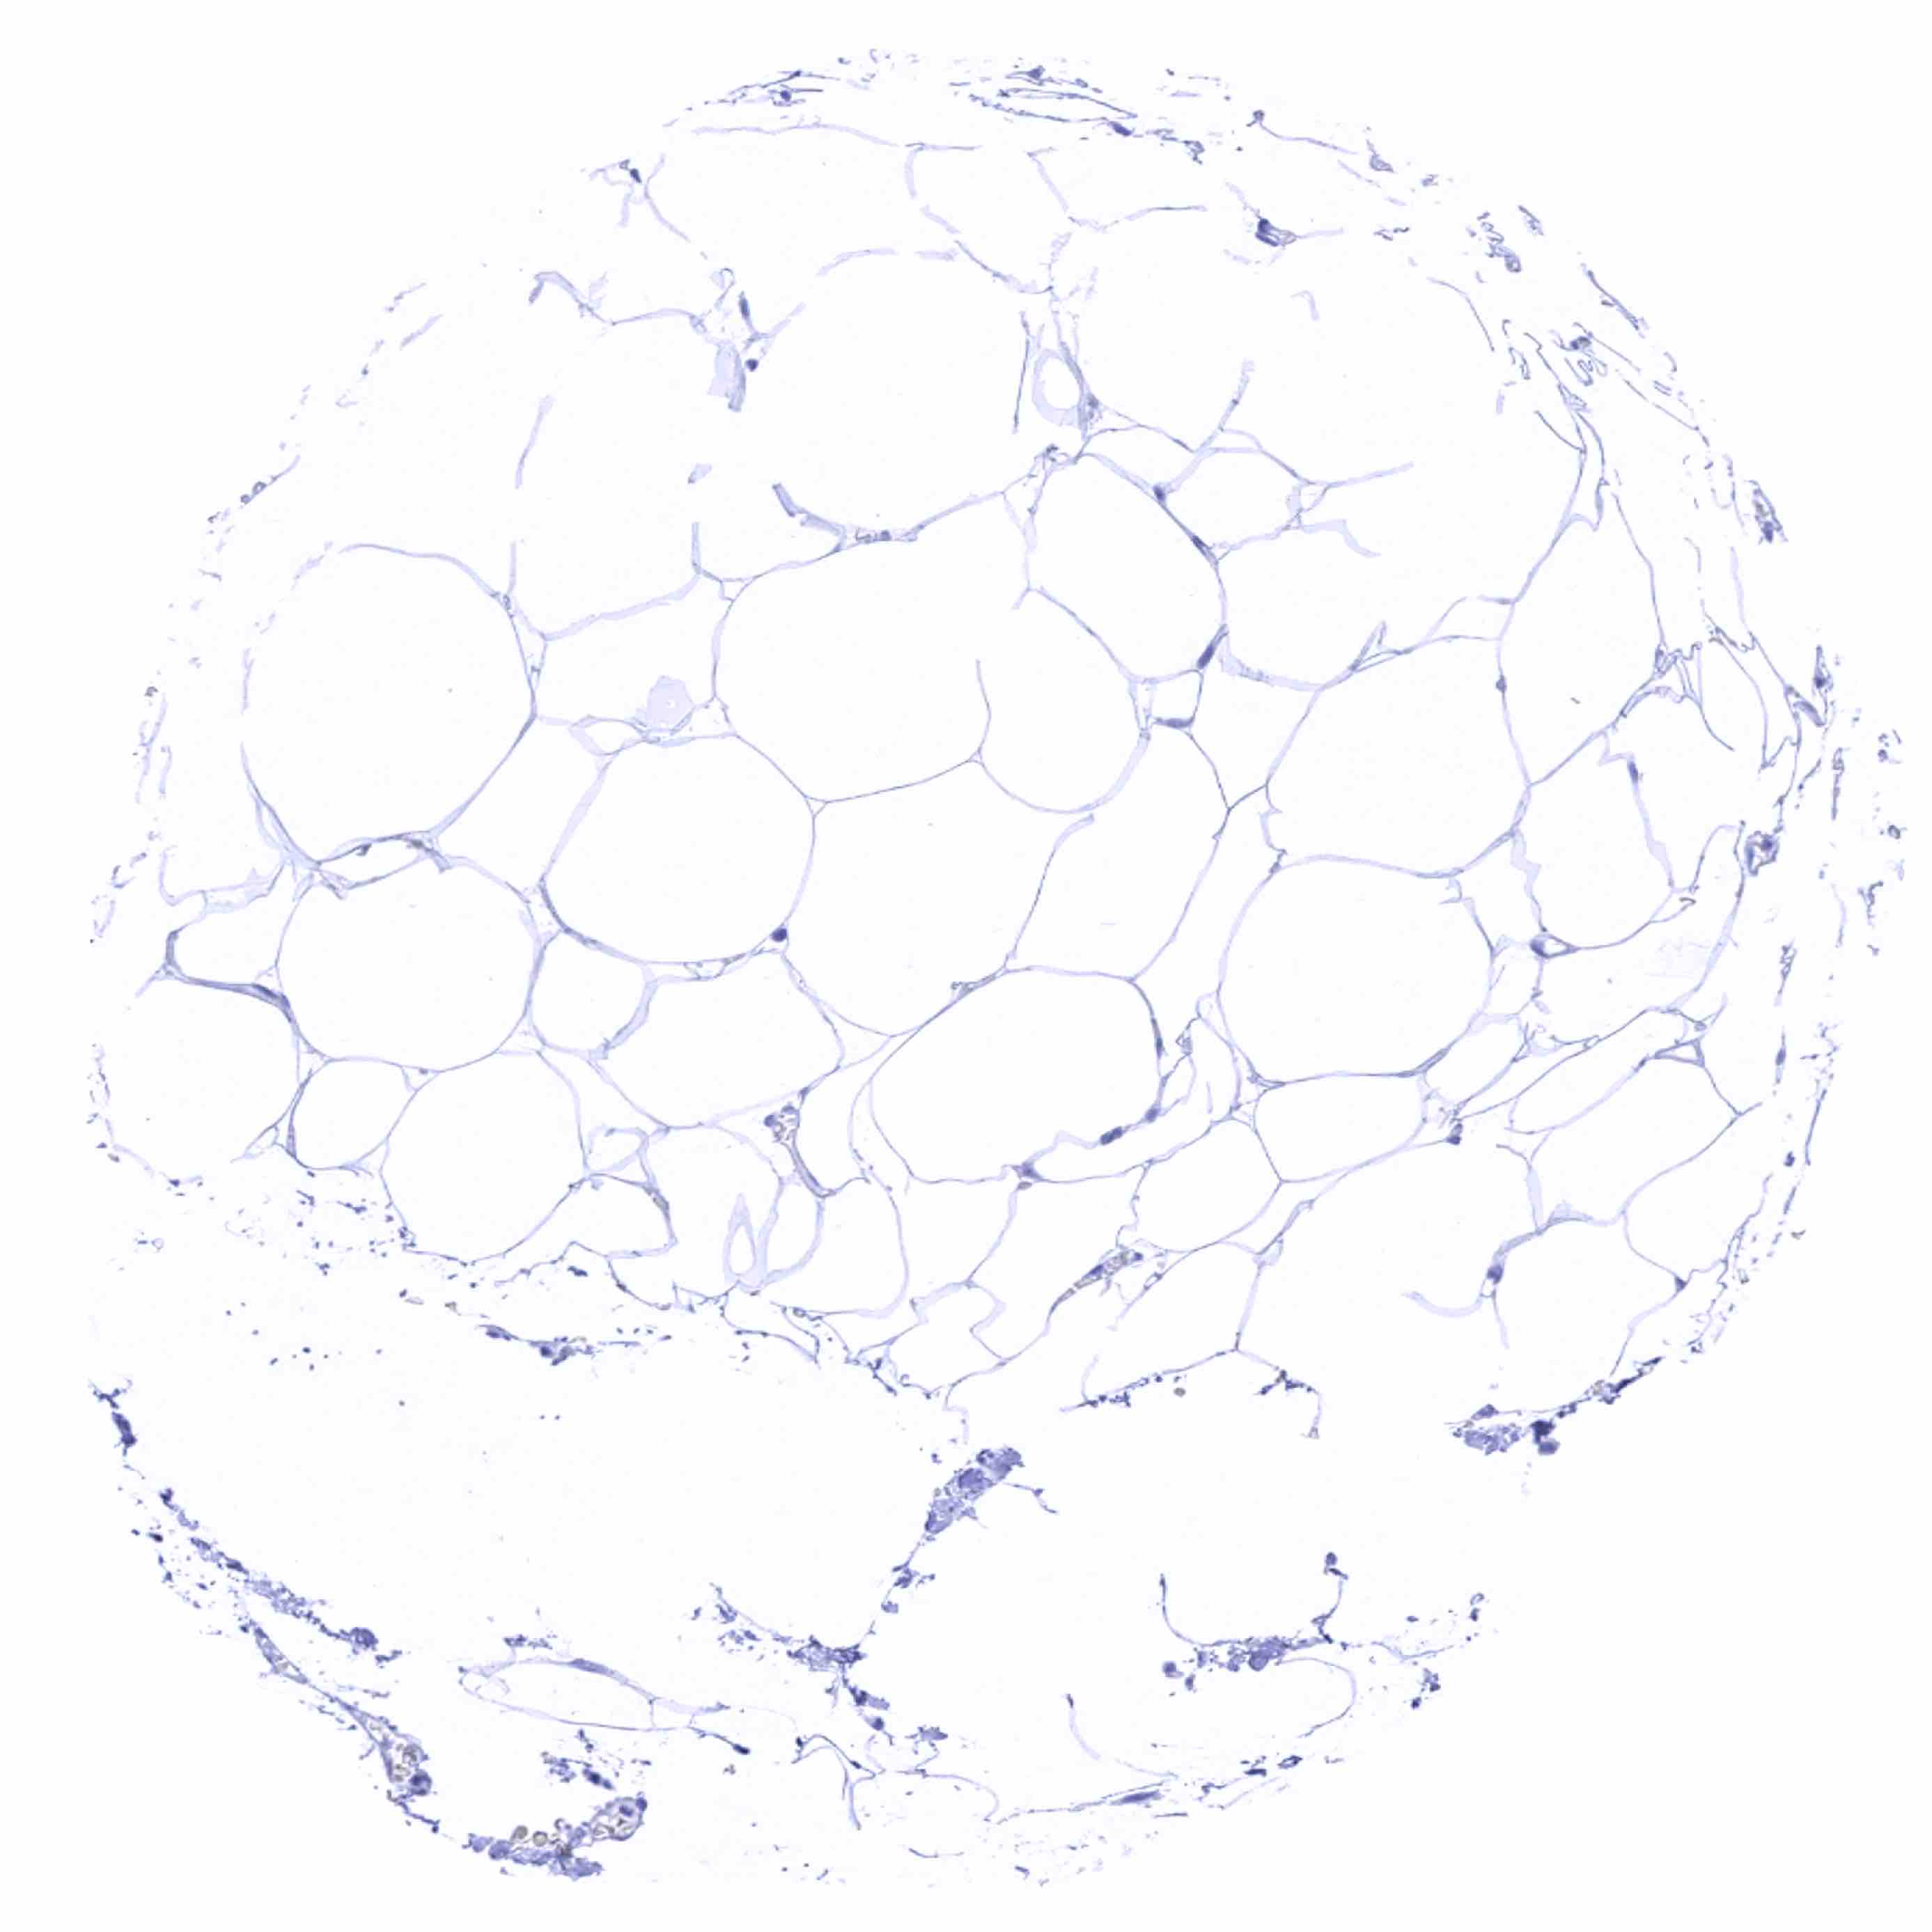

Fat